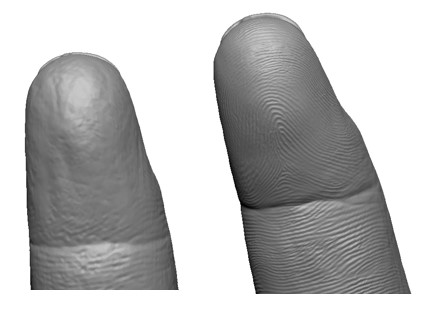

The Master of Science program in Clinical Anaplastology (CA) provides students with knowledge to succeed as clinicians providing facial, ocular (eye), and non-weight bearing somatic (body) prostheses, as well as designing 3D patient-matched models, surgical templates and other 3D printed clinical models.

- Examples of the work created